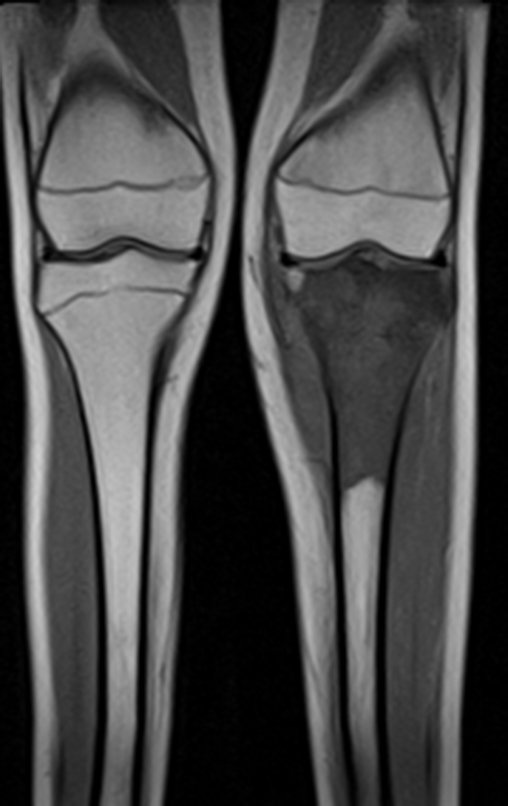

Prótesis Parcial de Tibia. Paciente femenina, 12 años, fecha de nacimiento 18 de marzo de 2003, comenzó en abril con dolor y cojera, consultó en varios centros y fue tratada con analgésicos.

Ingresó en el hospital en mayo y se sometió a una biopsia por punción. El informe anatomopatológico indicó osteosarcoma central convencional localizado, con cultivos negativos. Se le realizó estadificación con TC de tórax, gammagrafía ósea de todo el cuerpo y resonancia magnética del miembro inferior derecho. Se le realizaron tres ciclos de quimioterapia neoadyuvante con Platino y Doxorrubicina, con buena respuesta.